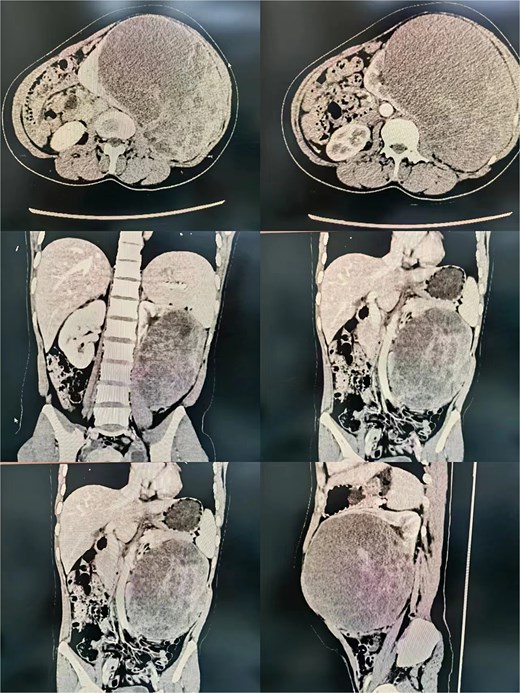

A 36-year-old female with no comorbidities presented with progressive abdominal pain for 1 month. Initial imaging suggested pancreatic origin, but contrast-enhanced CT localized a 14 × 13 × 12 cm heterogeneous left renal mass concerning for malignancy (Fig. 1). Laboratory workup revealed anemia (Hb 88 g/l), leukocytosis (12.31 × 109/l), and sterile pyuria (WBC 814.1/μl). No hormonal hypersecretion was documented.